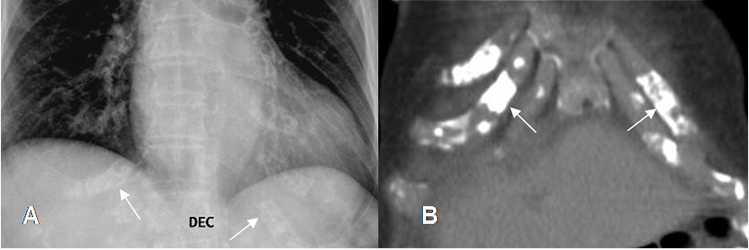

Fig 13. Fractura oculta.

A: Rx PA. Interposición de la silueta cardiaca y aorta descendente, que impide la valoración de la columna dorsal inferior.

B: TAC axial. Fractura no sospechada en la Rx, de la unión costovertebral izquierda.